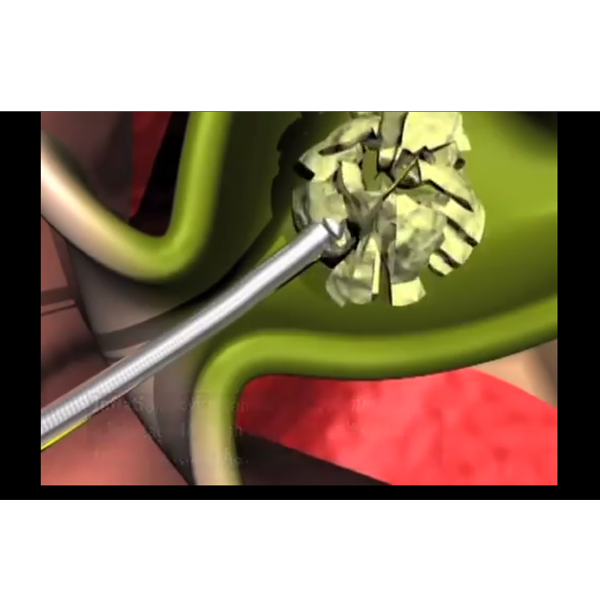

Illustration showing proper positioning of scope below papillary opening when removing the basket

Animation shows Trapezoid RX Basket and Alliance II Inflation Handle capturing and crushing a large stone in the CBD

Alliance™ II Inflation Handle: Used with Trapezoid Basket to mechanically crush large stones